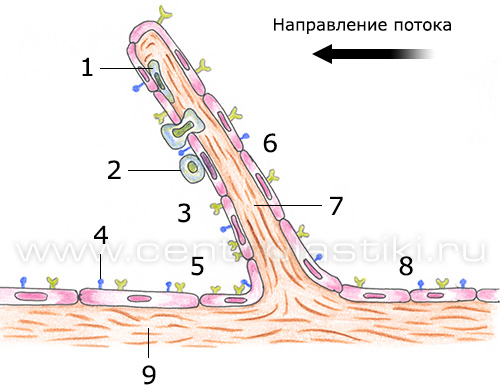

Варикоз - причины и механизмы развитияВарикозная болезнь – это полиэтиологическое заболевание, часто возникающее из-за генетической предрасположенности (так называемая слабость соединительной ткани), гормонального влияния (беременность, прием гормональных препаратов), конституции тела (чаще заболевают люди высокого роста и те, чья масса тела превышает норму), расовой принадлежности (например, варикозом редко страдают люди желтой и черной расы).  На возникновение заболевания существенно влияют образ жизни и характер трудовой деятельности («стоячая» работа, тяжелые физические нагрузки, частое ношение высоких каблуков).  Все этиологические факторы варикоза условно делятся на две группы: предрасполагающие и производящие. Предрасполагающими факторами называют те, что влияют на морфологические и функциональные изменения стенок поверхностных вен и клапанов. Эти факторы сами по себе не приводят к расширению вен, но создают условия, в которых образуется анатомическая и функциональная неполноценность системы поверхностных вен ног.  Производящие факторы представляют собой многочисленную группу, и среди них выделяют три ведущих механизма, ответственных за венозную гипертензию нижних конечностей: 1. Нарушение оттока крови из венозной системы нижних конечностей (из-за высокого роста, статической нагрузки, внутрибрюшного давления, кашля, запора, беременности). 2. Переход крови из глубоких вен в поверхностные приводит к расширению глубоких вен, что влечет за собой относительную клапанную недостаточность и варикоз поверхностных вен. 3. Переход крови из системы артериального кровотока в поверхностные вены по артериовенозным коммуникациям, которые в нормальном состоянии не функционируют, а служат лишь для ситуаций тяжелой мышечной работы, действия высокой температуры, и т.д.). В настоящее время механизмы повреждения стенок вен при варикозе объясняются при помощи феномена лейкоцитарной агрессии. При гипертензии нормальная вена, которая обладает значительным резервом возможностей, реагирует на изменение ситуации повышением своего тонуса. Если же возникла врожденная или приобретенная слабость венозной стенки и просвет вены необратимо увеличился, то этого не происходит. Современные представления о механизмах повреждения стенки вены при варикозной болезни основываются на феномене лейкоцитарной агрессии. Нормальная вена, обладая значительными резервными возможностями, реагирует на гипертензию повышением своего тонуса. Этого не происходит при врожденной или приобретенной слабости мышечно-эластических образований венозной стенки, когда в ответ на периодическое или постоянное повышение внутрисосудистого давления постепенно развивается необратимое увеличение просвета вены.  1 - Макрофаг; 2 - Миграция и адгезия макрофага; 3 - Клапанный синус; 4 - Молекулярная экспрессия; 5 - Проксимальный отдел вены; 6 - Нижняя поверхность створки клапана; 7 - Венозный клапан; 8 - Дистальный отдел вены; 9 - Венозная стенка. Замедление кровотока приводит к краевому стоянию лейкоцитов, которое происходит из-за их плотного контакта с эндотелийным слоем, на поверхности которого начинают экспрессироваться адгезивные молекулы, деятельность которых стимулируется медиаторами воспаления. В результате образуется хронический процесс воспаления, к которому присоединяется патогенная микрофлора и развитие инфекции. Стенка варикозной вены теряет тканевый активатор плазминоген, это снижает местную фибринолитическую активность, возрастает риск спонтанного тромбообразования и развития острого варикотромбофлебита. Повышается проницаемость капиллярной системы и внутрикапиллярное давление, это приводит к просачиванию из сосудистого русла в ткани не только воды, электролитов, и различных белковых фракций, но и форменных элементов крови. Геморрагическое пропитывание усиливает склеротические процессы в тканях и служит причиной возникновения характерной гиперпигментации кожи.  Флебостаз усиливает сопротивление венозного конца капиллярного русла, лимфатические капилляры перегружаются, происходит расширение лимфатических сосудов, объем оттекающей лимфы увеличивается. Лимфатическая система оказывается неспособна к достаточному дополнительному дренажу из тканей пораженной конечности: развивается отек, а белки плазмы и лейкоциты проникают в околососудистые ткани. Возникает процесс полимеризации фибриногена вокруг капилляров, происходит возникновение периваскулярных фибриновых муфт, которые ещё больше нарушают трофику и способствуют развитию язв. Местные медиаторы воспаления провоцируют появление разнообразных аутоаллергических реакций, которые провоцируют склерозирующий лимфангоит. Сосуды лимфы перестают ритмически сокращаться и становятся неподвижными трубками. Стенки сосудов становятся более проницаемыми, сквозь них в окружающие ткани просачивается богатая белками лимфа, развивается фиброз. Отек становится все более и более стойким и может превратиться во флебогенную слоновость. Также нарушается центральная гемодинамика, поскольку в варикозно-деформированных венах содержится от 1,5 до 3-х литров крови. Это ведет возникновения компенсаторного увеличения ОЦК (гиперволемии) и перегрузке венозного русла. Миокард изменяет свое функционирование, поскольку при ортостазе, если снижается сердечный индекс, то отсутствует компенсация его тахикардией, а это ведет за собой недостаточность системного кровообращения. При отсутствии лечения варикоз переходит в стадию трофических изменений мягких тканей ног вплоть до образования трофических язв. |